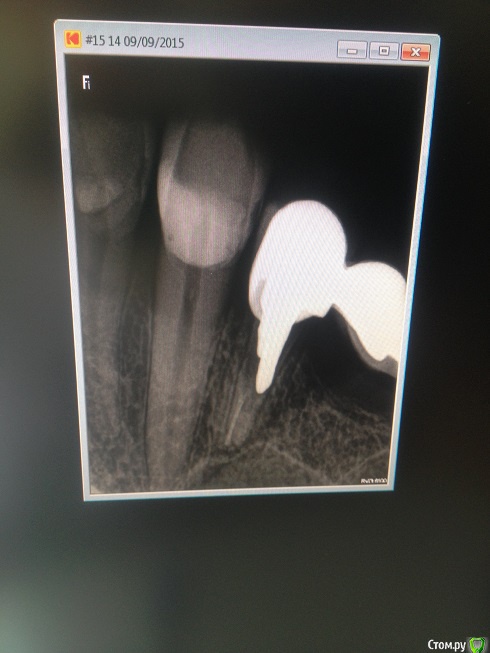

salah Опубликовано 9 сентября, 2015 Поделиться Опубликовано 9 сентября, 2015 Здравствуйте заболел зуб под мостом при надкусывании сделала снимок врач сказал что зуб под коронкой сгнил, но от десны не пахнет и так зуб не болит. Стоит ли снимать мост и удалять зуб? И еще врач советовал сделать оптг не знаю зачем это нужно? Ссылка на комментарий

anvladd Опубликовано 9 сентября, 2015 Поделиться Опубликовано 9 сентября, 2015 зуб на выход. 5 Ссылка на комментарий

red_butler Опубликовано 9 сентября, 2015 Поделиться Опубликовано 9 сентября, 2015 Стоит ли снимать мост и удалять зуб? Да И еще врач советовал сделать оптг не знаю зачем это нужно? Для диагностики Ссылка на комментарий

Чертков Александр Опубликовано 10 сентября, 2015 Поделиться Опубликовано 10 сентября, 2015 зуб на выход.+1 Ссылка на комментарий